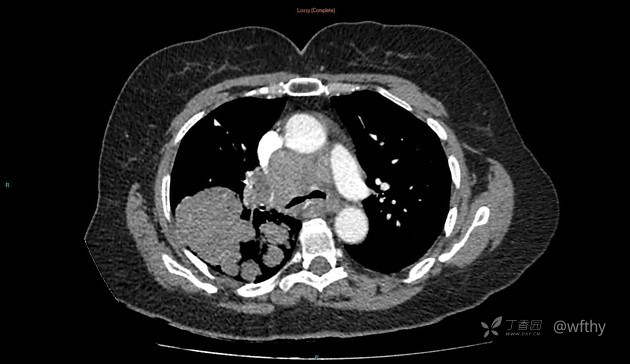

病例女65,头部肿块